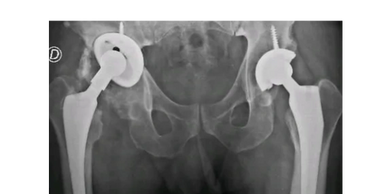

Mirá cómo recuperamos la movilidad en un caso de artrosis severa y deformidad acetabular mediante tecnología 3D de alta precisión. Planificación preoperatoria en 3D para cirugía de cadera con artrosis severa e importante deformidad acetabular. Se imprimieron biomodelos en 3D y guías para la correcta colocación de los componentes protésicos. De esta manera, se logró restaurar la longitud de las piernas y se eliminó el dolor invalidante que presentaba el paciente.

Cirugía compleja de reemplazo total de cadera.

Paciente con artrosis severa y deformidad ósea que dificultaba la colocación acetabular. Con tomografía realizamos planificación 3D y diseñamos una guía quirúrgica personalizada impresa en 3D. En quirófano replicamos el plan: posicionamiento preciso del componente y restauración del centro de rotación. La tecnología 3D aporta más precisión, seguridad y predictibilidad en casos complejos.